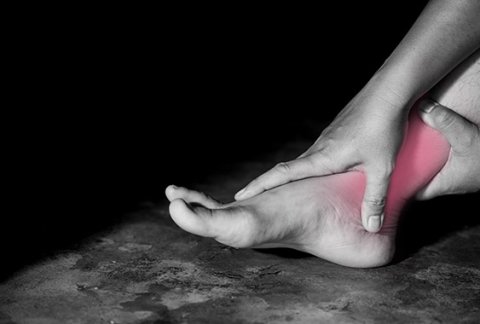

Plantar fasciitis exercises for effective heel pain relief

Plantar fasciitis is a common condition causing heel pain, affecting millions ...

Plantar Fasciitis Treatment

What is plantar fasciitis?Also known as Policeman’s heel, plantar fasciitis is ...

Orthotics for Plantar Fasciitis Pain

What is plantar fasciitisPlantar fasciitis is one of the most common ...